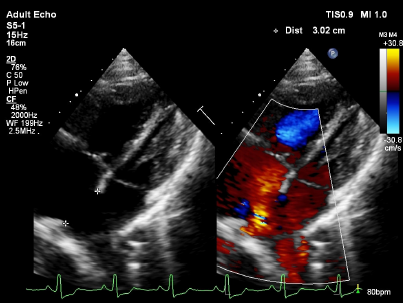

Transthoracic echocardiography showed dilated right atrium, right ventricle with a large atrial septal defect (ASD) with bi-directional shunt and severe pulmonary valve stenosis (Figures 2–4). Bubble's study confirmed the diagnosis of atrial septal defect (Figure 5) Parasternal long-axis view M-mode showed right ventricular hypertrophy of 9mm (Figure 6). Further plan for trans-esophagealechocardiography was discussed with patient but due to financial constraints as a foreigner, he decided to continue investigations in his home country. The patient was rehydrated with intravenous fluid therapy and was discharged with referral letter to home country.

Figure 2 Large ASD (3cm).